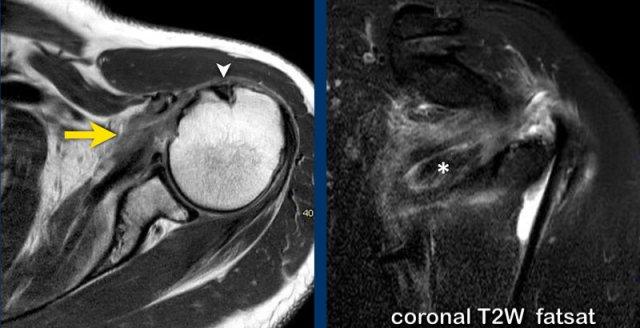

Chụp MRI khớp với chuỗi xung T1W xóa mỡ mặt phẳng axial và chuỗi xung PD mặt phẳng coronal.

Ghi nhận hình ảnh trật gân cơ nhị đầu về phía trong, nằm trong gân cơ dưới vai (mũi tên).

Có hình ảnh rách bán phần gân cơ dưới vai.

Trên ảnh PDW, ghi nhận khoảng trống chứa dịch tại vị trí bám tận xa của gân cơ trên gai và thuốc tương phản từ lan vào khoang dưới mỏm cùng vai – dưới cơ delta, phù hợp với hình ảnh rách toàn phần gân cơ trên gai.